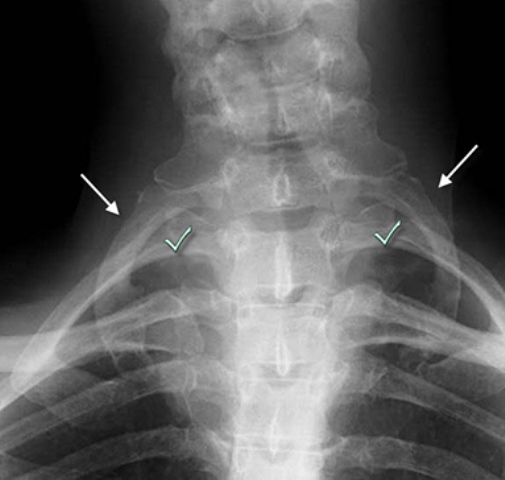

ب) دنده گردنی چیست؟

گاهی اوقات پایینترین مهره گردن یعنی مهره هفتم هم یک دنده دارد که البته به اندازه دنده های سینه ای نیست و از آنها کوچکتر است. پس این دنده در بالای دنده اول سینه ای قرار میگیرد. به این دنده اضافی دنده گردنی میگویند و از هر 200 انسان در یک نفر وجود دارد. پس این انسان ها بجای 12 جفت دنده 13 جفت دنده دارند. وجود دنده گردنی ممکن است باعث ایجاد درد در گردن و دست و بیحسی یا مور مور شدن دست شود. دنده گردنی میتواند در یک طرف گردن باشد و یا میتواند دو طرفه باشد . همانطور که گفتیم یک سر این دنده به مهره هفتم گردنی متصل شده است ولی سر دیگر آن معمولا آزاد است. البته گاهی اوقات سر دیگر آن با دنده اول سینه ای مفصل میشود و یا گاهی اوقات از سر این دنده گردنی یک نوار بافتی محکم خارج شده و به دنده اول متصل میشود .

اهمیت این فضای توراسیک اوتلت در بیماری است که به علت تنگ شدن این فضا ایجاد شده و به آن سندرم توراسیک اوتلت Thoracic outlet syndrome میگویند. این فضا به علل مختلفی میتواند تنگ شود. تنگ شدن آن معمولا در طرف راست یا چپ است ولی میتواند دو طرفه هم باشد. بدنبال تنگ شدن این فضا اعصاب شبکه بازویی تحت فشار قرار میگیرند و فشار به این اعصاب، علائمی را برای بیمار ایجاد میکند. گاهی هم ممکن است شریان یا ورید ساب کلاوین هم در این فضا گیر کنند که فشار به آنها هم میتواند علائم دیگری را برای بیمار ایجاد کند

اهمیت دنده گردنی اینست که وجود آن یکی از شایعترین علل ایجاد سندرم توراسیک اوتلت است .

یکی از علل شایع تنگ شدن فضای توراسیک اوتلت، وجود دنده گردنی است. پس اهمیت دنده گردنی اینست که میتواند فضای توراسیک اوتلت را تنگ کرده و به اعصاب یا عروقی که از این ناحیه عبور میکنند فشار ایجاد کند. البته اینطور نیست که هر کسی که دنده گردنی دارد این مشکلات را هم داشته باشد. از هر ده نفری که دنده گردنی دارند فقط در یک نفر آنها به اعصاب یا عروق فشار وارد شده و مشکل دار میشوند .

.jpg)

در بعضی افراد یک نوار بافتی محکم از نوک زائده عرضی مهره هفتم گردنی خارج شده و به دنده اول سینه میچسبد. این نوار بافتی در فضای توراسیک اوتلت است و میتواند مانند دنده گردنی به اعصاب و عروق فشار وارد کند. گاهی اوقات هم فقط زائده عرضی مهره هفته گردنی بلندتر از معمول بوده و در فضای مورد نظر به عروق و اعصاب فشار وارد میکند .